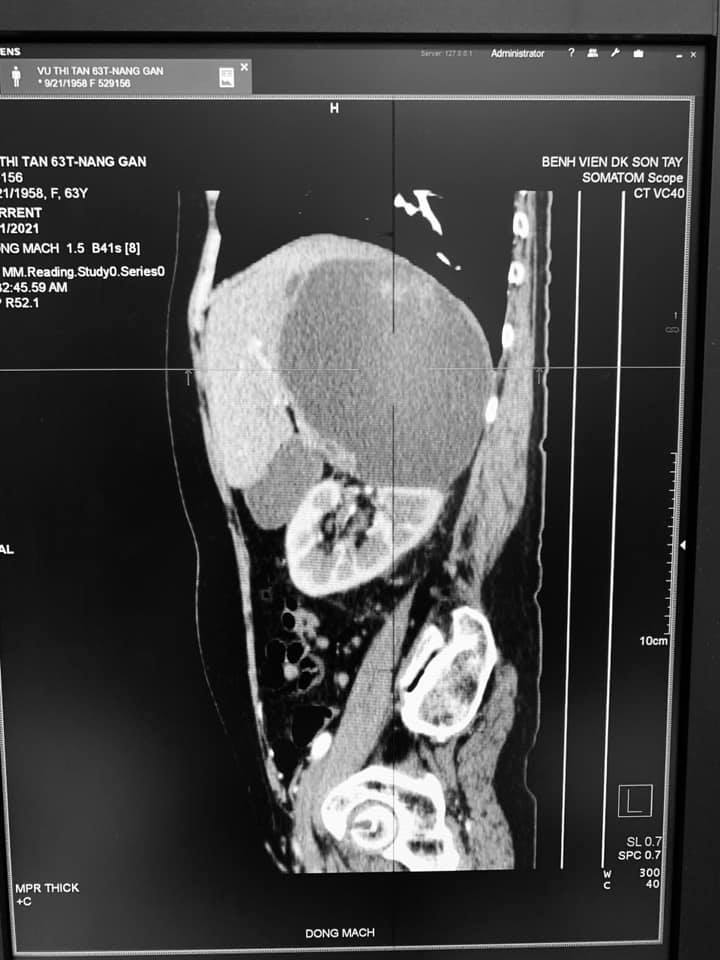

Qua hỏi bệnh, thăm khám và làm các xét nghiệm chẩn đoán cận lâm sàng được biết bệnh nhân có tiền sử Nang gan phải đã phẫu thuật nang gan 2 lần.( lần 1 năm 2019, lần 2 năm 2021), Xét nghiệm huyết học, sinh hóa các trị số bình thường, kết quả siêu âm: Hình ảnh nang gan phải TD xuất huyết trong nang, kết quả chụp cắt lớp vi tính : Hình ảnh nang gan chảy máu( KT 11x12cm).